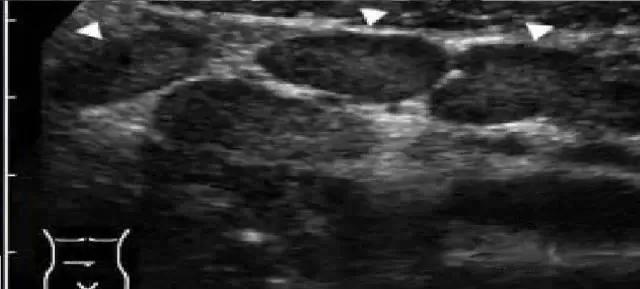

体外超声碎石(ESWL)已成为治疗肾结石的首选方法之一。这种非侵入性技术通过体外碎石机产生冲击波,聚焦后对准结石,经过多次释放能量将结石击碎成小碎块,随后这些碎块随尿液排出体外。

ESWL的操作相对简单,患者只需躺在手术台上,通过超声或X线定位结石位置。治疗过程中,患者可能会听到机器发出的轻微砰砰声,医生会从低强度开始逐渐增加冲击波强度。整个过程通常持续约45分钟,大多数情况下无需麻醉。